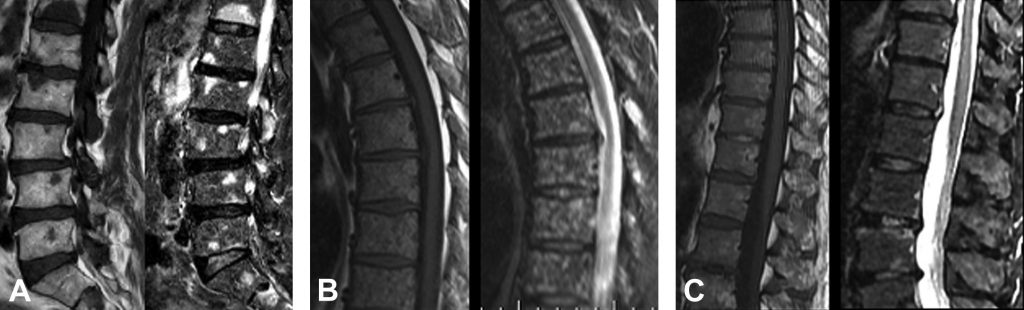

Fig. 80.2 Myélome.

IRM du rachis (coupe sagittale T1 et STIR) montrant trois formes d’infiltration médullaire ; les lésions apparaissent toutes en hyposignal T1 et en hypersignal STIR. Forme nodulaire (A) : lésions focales mesurant au moins 5 mm. Forme micronodulaire (B) : lésions de petite taille donnant un aspect tacheté de la moelle osseuse (« aspect poivre et sel »). Infiltration diffuse non nodulaire (C).

Plusieurs types de lésions (cf. figure 80.2) apparaissant toutes en hyposignal T1 et hypersignal T2 peuvent être observés :

- nodulaires : lésions focales d’au moins 5 mm ;

- micronodulaires : lésions de petite taille donnant un aspect tacheté de la moelle osseuse (aspect « poivre et sel ») ;

- diffuses : infiltration diffuse homogène ou hétérogène de la moelle osseuse (remplacement médullaire complet).